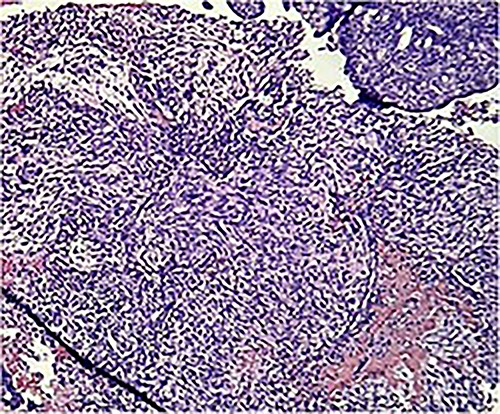

Macroscopically, an amorphous uterus weighing 397 g and measuring 12 × 9 × 7.5 cm with a brown serosa, and multinodular violaceous areas was examined. When incised, the endometrial cavity was occupied by a whitish polypoid mass of 8 × 5 cm which invaded the myometrium. In addition, multiple firm whitish nodules ~2 × 1.5 cm in diameter were identified. Bilateral ovaries and fallopian tubes appeared to be of normal morphology and size. Histologically, there was evidence of epithelial and sarcomatous components (Figs 1 and 2), and the epithelial component developed atypical glands (Fig. 3). The diagnosis of MMMT was given due to histologic findings.

Photomicrograph shows epithelial components that form atypical glands and solid nodules with a sarcomatous component (H & E stain ×10).